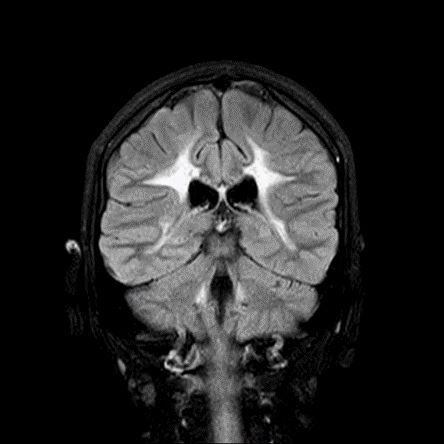

- A) Aksiyel T2A ve koronal T2A sekanslarda sentrum semiovale, korona radiata ve bazal ganglionlar düzeyinde bilateral frontoparietal derin periventriküler beyaz cevherde birleşme eğilimi gösteren hiperintens gliotik sinyal değişiklikleri (oklar) ve aksiyel T2A serilerde servikal spinal kordda posterior kolonda, lateral kesimlerde sinyal artımları (oklar) izlendi.

- LBSL, karakteristik radyolojik özelliklere sahiptir. MRG’de tipik olarak bilateral ve simetrik beyaz cevher sinyal değişiklikleri görülürken, subkortikal U lifleri, internal kapsülün posterior kolları, trigeminal sinir traktları, serebellum, korpus kallozumun spleniumu, medulla oblongata ve omurilikteki dorsal kolonlar ile lateral kortikospinal traktlar genellikle korunur.

- Etkilenen bölgelerde T1’de hipointens, T2/FLAIR’da hiperintens sinyal değişiklikleri izlenir. DWI’de lezyonların periferinde kısıtlı difüzyon görülebilir. MRS’de beyaz cevherde laktat artışı saptanabilir, ancak bu her hastada mevcut değildir.

- LBSL tanısında majör kriterler; subkortikal U lifleri korunmuş serebral beyaz cevher, servikal düzey dahil omurilik dorsal kolonları ve lateral kortikospinal traktlar, medulla oblongata piramitleri veya medial lemniskus dekusasyonu tutulumu iken; minör kriterler korpus kallozum spleniumu, internal kapsül posterior kolu, superior ve inferior serebellar pedinküller, trigeminal sinir traktları, mezensefalik trigeminal yollar, medulla oblongata anterior spinosebellar traktları ve serebellar beyaz cevherdeki sinyal değişiklikleridir.